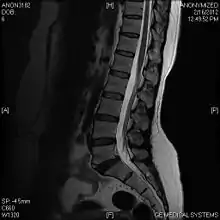

Limbus vertebra

A limbus vertebra is a bone tubercle formed by bone trauma on a vertebral body, bearing a radiographic similarity to a vertebral fracture. The anterior-superior corner of a single vertebra is the common site for this defect although it can also be seen at the inferior corner as well as the posterior or anterior margin. Anatomically, it is assumed to be an intra-vertebral body herniation of the disc material occurring during adolescent growth spurt when the ring apophysis has not yet fused. It was first described by Schmorl in 1927[1] and later in detail by Leif Sward and Adad Baranto.

Viewed in a lateral radiograph, it appears as a triangular shaped bone fragment, not unlike an anterior lip fracture, but with softer edges.

Limbus vertebra is not always symptomatic, but severe cases may lead to more serious pathological conditions and chronic pain. In rare instances, a posterior limbus vertebra has been described causing radiculopathy due to nerve root compression. [2]